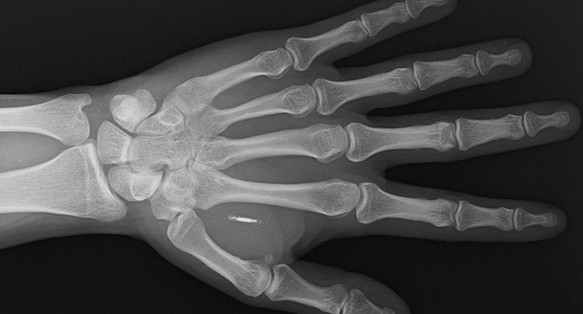

El microchip de Walletmor pesa menos de un gramo y es un poco más grande que un grano de arroz. Está compuesto con una antena recubierta de un biopolímero, un material de origen natural similar al plástico.